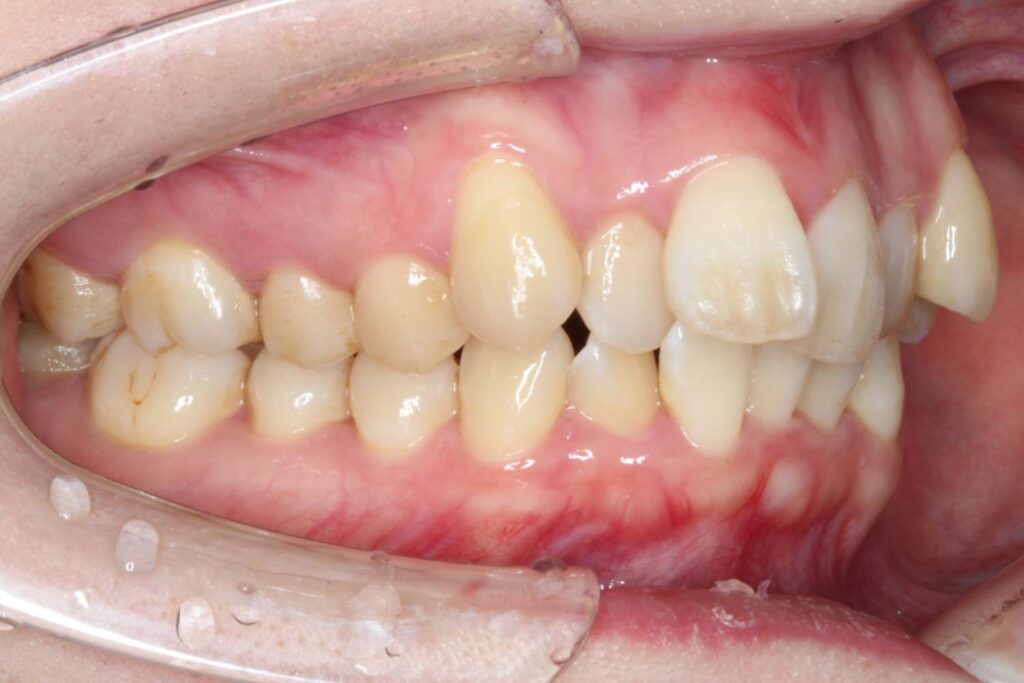

前歯に叢生があり、特に右上の前歯は前方に突出していて目立ってしまっています。

また、上顎の犬歯は「八重歯」と呼ばれる状態で、唇をよく噛んでしまったり、口内炎ができてしまうとのことでした。

奥歯の噛み合わせは、下顎に対して上顎が前方にずれてしまっています。

Before